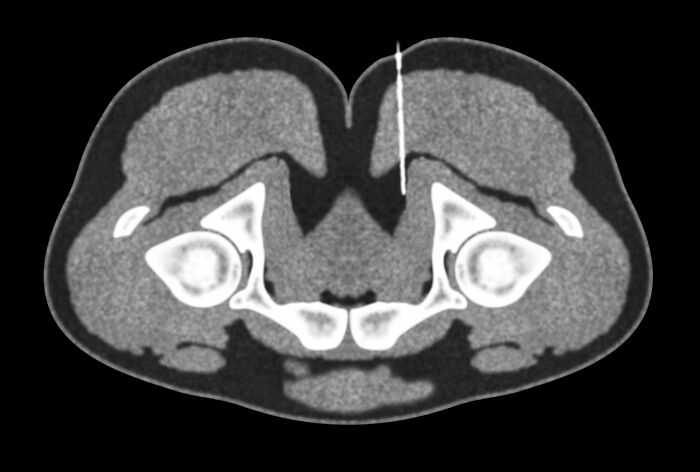

When you get a kidney transplant, they leave the old one in there and stick the new one in your pelvis. There are people walking around with three or four kidneys.

Jennacyde153:

My colleague’s dad just got 2 new ones so now he has 4. My kid only has 1 kidney but it’s as big as an adult kidney.